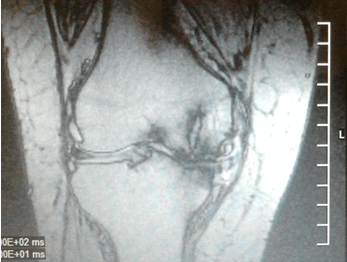

(Справа) МРТ, аксиальная проекция, режим протонной плотности: полнослойный дефект хряща с вовлечением обеих фасеток надколенника у этого же пациента. Такая картина тяжелого поражения может не соответствовать результатам менее информативной рентгенографии. (Слева) МРТ, корональная проекция, режим протонной плотности с подавлением сигнала от жира: не визуализирующиеся при рентгенографии свободные тела. Определяется глубокий фокальный дефект хряща.

(Справа) МРТ, сагиттальная проекция, режим Т2 с подавлением сигнала от жира: срез выполнен несколько медиальнее субхондрального остеофита, однако здесь определяется обширный дефект хряща нагружаемой зоны медиального мыщелка бедренной кости, наряду с признаками расслоения. Сигнал от субхондральных остеофитов достоверно ассоциируется с повреждением хряща. (Слева) МР-артрография, сагиттальная проекция, режим Т2 с подавлением сигнала от жира: определяется обширный дефект хряща в области блока, а также признаки отека костного мозга. Необходимо скрупулезно исследовать область блока, оценка протяженности повреждения которого может быть затруднена, поскольку его поверхность обычно не ортогональна плоскости исследования.

Рис. 1. Рентгенограмма и МРТ коленных суставов больной З.,62 лет. На рентгенограмме (А) выраженное сужение медиальных отделов суставной щели, краевые остеофиты, субхондральный склероз. На МРТ(Б) краевые приострения, выраженные дегегнеративные изменения в медиальных отделов субхондральной кости, выраженное истончение медиального отдела хряща. Дегенерация медиального мениска

Рис.2. Рентгенограмма и МРТ больной Б., 55 лет. А) Рентгенограмма не показывает признаки образования субхондральных кист. Б) МРТ (Т2) показывает кисту с высоким сигналом. Его легко можно дифференцировать от окружающего нормального костного мозга с низким сигналом

Вследствие нарушения равновесия между образованием нового строительного материала для восстановления хряща и его разрушением, хрящ истончается, на нем появляются язвы, обычно только в наиболее нагружаемой части сустава [5]. МРТ в сравнении рентгенографией более чувствительна в выявлении истончения хряща в латеральном отделе коленного сустава. На МРТ обнаруживалось истончение суставного хряща в латеральных отделах сустава, которые на рентгенограмме не проявлялись изменением суставной щели. Так как большая часть нагрузки приходится в медиальные отделы коленного сустава, изменения суставного хряща начинается с этой части сустава. На рентгенограммах в первую очередь суживается медиальные отделы суставной щели. При этом латеральные отделы суставной щели остаются не измененными и даже несколько расширяются. Это приводит к ложному выводу о интактности суставного хряща в этом отделе, изменения которого достоверно выявляется на МРТ (см.рис.3). Этим можно объяснить более низкую встречаемость изменения суставного хряща в латеральном отделе коленного сустава на рентгенограммах (23 суставах).

Рис.3. Рентгенограмма и МРТ больной Ш.,58 лет. А) Рентгенограмма показывает умеренное расширение латерального отдела суставной щели. Б)

МРТ показывает истончение хряща в этом же отделе